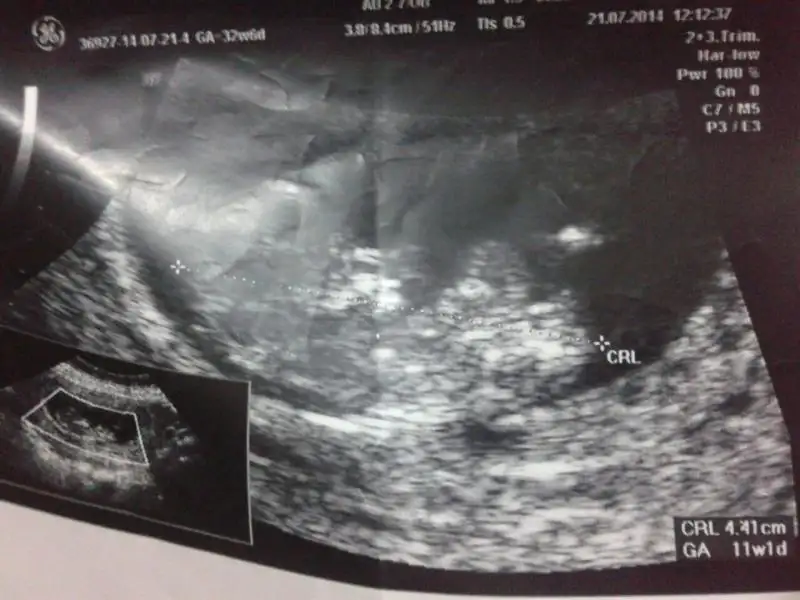

gönderdiğim resimleri yorumlarmısınız 11+1 günlük fotolar. şimdiden teşekkürederim

• $IMG-20140725-WA0001.webp

$IMG-20140725-WA0001.webp

26,1 KB · Görüntüleme: 99

• $IMG-20140725-WA0003.webp

$IMG-20140725-WA0003.webp

25,4 KB · Görüntüleme: 92